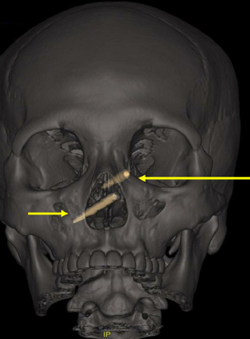

直到CT的结果出来,众人直接惊掉下巴,因为有两根异物从他的鼻子直接插入了他的头骨,而经过进一步检查,认定脑袋里的东西就是筷子。这真是纱布擦屁股,给白衣天使漏了一手。

所以,很有可能是打架的时候有人用筷子捅了他的鼻子,然后直接插进了头骨。但筷子插入的位置太深了,医生和他都没有发现鼻子里的异物,直到伤势过于严重才发现。

好在手术很成功,筷子被取了出来,只不过看到筷子的大小,我再次感到震惊,隔着屏幕都要痛死了。